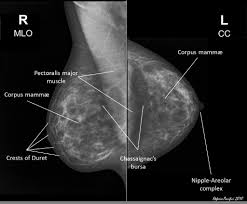

How Does Breast Cancer Look Like On A Mammogram / Mammogram Images Normal Abnormal And Breast Cancer : The outer edges of these cells look fuzzy or spiky (called spiculated).. Healthy mammograms can still vary in appearance. That makes it easy to detect abnormalities, which generally show up as white. If found in an area of rapidly dividing cells or grouped together in a certain way, they may be a sign of dcis or breast. A lump or tumor will show up as a focused white area on a mammogram. Dense breast tissue appears solid.

Breast Masses Cancerous Tumor Or Benign Lump from www.verywellhealth.com Even if you have a lump in only one breast, pictures will be taken of both breasts. This appears most commonly as streaking, known as linear enhancement. A woman's breast tissue also changes over time, and it is not uncommon for benign lumps, cysts or calcifications to form with age. Breast cancer can appear as a spiculated mass, cluster of tiny calcifications, smoothly marginated mass, area of subtle distortion or be invisible on. What does an abnormal mammogram look like? Cancer cells can remain within the milk ducts and this is considered as noninvasive cancer or ductal carcinoma in situ. Magnetic resonance imaging (mri) of the breast — or breast mri — is a test used to detect breast cancer and other abnormalities in the breast. The appearance of normal breast tissue on a mammogram varies from person to person, and no two mammograms look the same.

Mammogram Images Normal And Abnormal from www.verywellhealth.com Any area that does not look like normal tissue is a possible cause for concern. The appearance of normal breast tissue on a mammogram varies from person to person, and no two mammograms look the same. A woman's breast tissue also changes over time, and it is not uncommon for benign lumps, cysts or calcifications to form with age. What does cancer look like on a mammogram? Tumors may be benign or cancerous. Abnormalities such as cancerous tumors usually appear brighter because they are denser. Cancers may be seen as masses (like a ball, but usually with an irregular shape), areas of asymmetry that resemble normal tissue, calcifications (white specks), and/or areas of architectural distortion (imagine the puckering caused by pulling a thread in a piece of fabric). Calcifications are calcium deposits within the breast tissue and they look like small white spots.

Any area that does not look like normal tissue is a possible cause for concern. Invasive breast cancer can appear as a white patch or mass on a mammogram. You may notice dimpling or pitting, and the skin on your breast. A rash isn't the only visual symptom of inflammatory breast cancer. The milk ducts carry your breast milk from lobules, where milk is produced, to your nipple. Magnetic resonance imaging (mri) of the breast — or breast mri — is a test used to detect breast cancer and other abnormalities in the breast. A lump or tumor will show up as a focused white area on a mammogram. 1 the gray areas correspond to normal fatty tissue, while the white areas are normal breast tissue with ducts and lobes. A spiculated breast mass, which has spikes extending out from the main mass, is often highly suggestive of cancer. Macrocalcifications, which look like small white dots on a mammogram. It's so important to listen to the messages our bodies are telling. In addition to mammograms, ultrasound and mri may also be used to take a closer look at changes in the breast. Breast cancer can appear as a spiculated mass, cluster of tiny calcifications, smoothly marginated mass, area of subtle distortion or be invisible on.